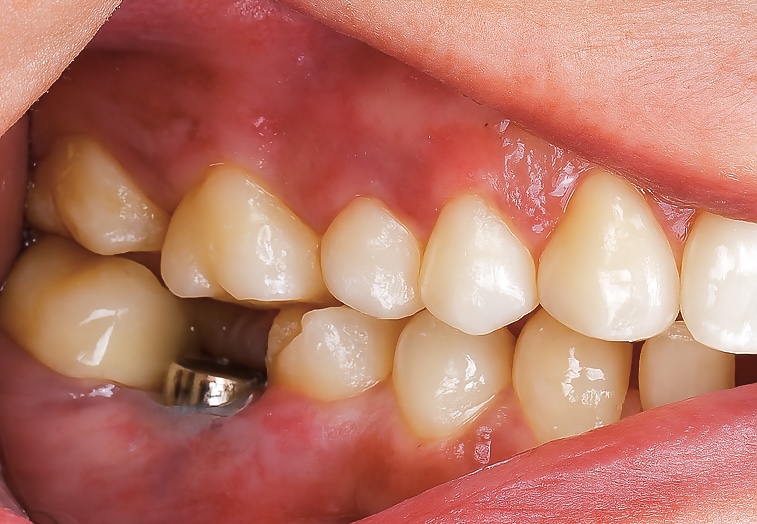

5️⃣ Try-In and Final Cementation

Fit, occlusion, and proximal contacts verified. The prosthesis was torqued to 25 Ncm per manufacturer instructions. The screw access was sealed with PTFE and composite (Fig 5).

Radiographic follow-up showed precise osseointegration, proper emergence profile, and marginal bone stability (Fig 6). The final prosthesis integrated seamlessly with natural dentition and provided excellent function and esthetics (Fig 7).